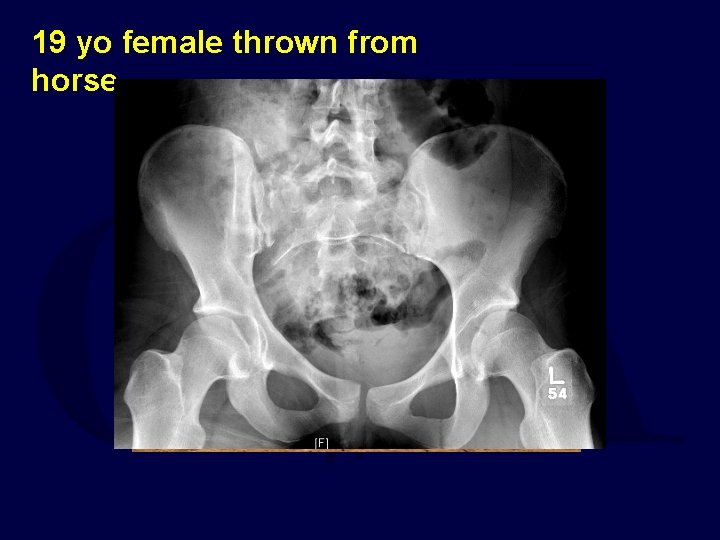

19 yo female thrown from horse